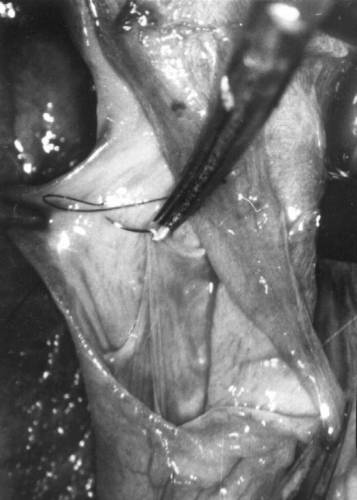

Этап микрохирургической реконструкции несостоятельного венозного клапана с различным уровнем комиссур.